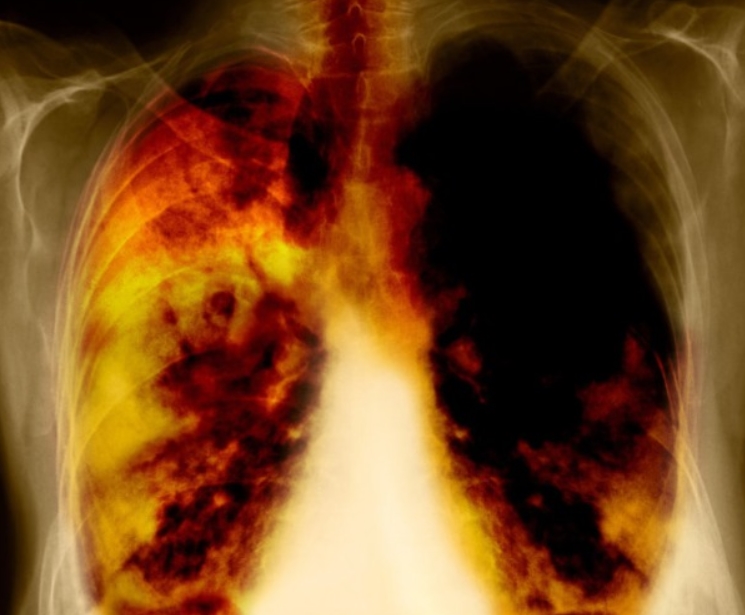

엑스레이를 보면 검고 하얀 그림처럼 보여요. 검은 부분은 공기가 많은 곳, 하얀 부분은 단단한 조직이에요. 이런 밝고 어두운 차이를 ‘음영’이라고 부릅니다. 폐처럼 공기가 가득한 부위는 검게, 뼈는 하얗게, 그리고 물이나 염증이 차면 회색빛으로 보이지요.

한번은 가족 중 한 분이 감기인 줄 알고 병원에 갔는데, 엑스레이를 본 의사 선생님이 “오른쪽 아래 음영이 진하네요”라며 흉부 엑스레이로 알수있는것 폐렴을 의심하셨어요. 실제로 약간의 염증이 있었던 거죠. 이렇게 음영은 그림자처럼 보여도, 그 속엔 우리 몸의 변화가 담겨 있어요. 뿌연 음영이 작게라도 생기면 “왜 그런 걸까?” 하고 한 번쯤 더 살펴볼 필요가 있습니다.

폐렴은 엑스레이에서 가장 자주 발견되는 질환 중 하나예요. 정상적인 폐는 까맣게 보이지만, 염증이 생기면 하얗게 변합니다. 의사들은 이를 보고 ‘침윤(염증이 번진 상태)’이라고 표현해요.

흉부 엑스레이로 알수있는것 폐렴의 종류에 따라 모양도 달라요. 한쪽 폐 전체가 하얗게 보이면 ‘엽성 폐렴’, 군데군데 얼룩처럼 보이면 ‘기관지 폐렴’일 수 있어요. 예전에 제 친구가 독감 후 기침이 너무 오래가서 병원에 갔는데, 엑스레이에 하얀 구름처럼 음영이 보여 폐렴 진단을 받았죠. 약을 꾸준히 먹고 다시 찍었을 땐 그 구름이 걷힌 것처럼 깨끗했어요. 이렇게 눈에 보이는 회복의 흔적이 참 다행스럽습니다.